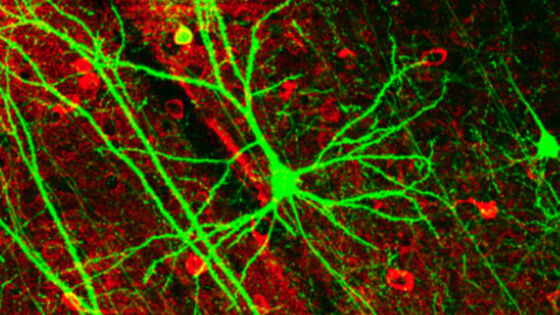

Мозг использует электрические импульсы для обмена сигналами, и человечество уже научилось стимулировать различные области этого органа при помощи специальных имплантатов. Теперь же исследователи пришли к выводу, что осуществлять коммуникацию с мозгом можно без помощи массивных устройств, но посредством введения наночастиц. Авторы нового исследования, результаты которого изложены в статье журнала Future Medicine, уверены, что методика стимуляции наночастицами поможет не только в лечении некоторых заболеваний мозга, но однажды позволит осуществить прямой обмен данными между сознанием и компьютером. Для коммуникации с мозгом на его "языке" (то есть через отправку электронных импульсов) учёные предлагают использовать магнитоэлектрические наночастицы. Они реагируют на внешние магнитные поля, в результате чего генерируется поле электрическое. Если такие наночастицы находятся рядом с нейронами, то создаваемое электрическое поле налаживает коммуникацию между клетками. Чтобы проверить данную гипотезу, ведущий автор нового исследования Сахрат Хизроев (Sakhrat Khizroev) и его коллеги из Флоридского международного университета в Майами провели эксперимент. Учёные ввели 20 миллиардов наночастиц в мозг мышей. Затем они активировали магнитное поле для индуцирования электрического поля. Электроэнцефалограмма показала, что область мозга грызунов, окружённая наночастицами, активирована, что указывает на то, что электрическое поле, созданное этими частицами, спровоцировало коммуникацию между нейронами. "Когда магнитоэлектрические наночастицы подвергаются воздействию даже крайне низкочастотного магнитного поля, они генерируют своё собственное локальное электрическое поле на той же частоте. В свою очередь электрическое поле может непосредственно соединяться с электрической схемой нейронной сети мозга", — поясняет Хизроев. Целью исследовательской группы является создание такой системы, которая обеспечила бы одновременную визуализацию мозговой активности и точную доставку медицинских препаратов. Поскольку наночастицы по-разному реагируют на различные частоты магнитного поля, они могут быть настроены и на высвобождение лекарств. К сегодняшнему дню эксперименты команды Хизроева уже успели продемонстрировать, что массив наночастиц, управляемый магнитным полем, способен точно доставить лекарства от ВИЧ, а также препарат паклитаксел, предназначенный для борьбы с раковыми опухолями. В будущем подобная методика может также быть использована для создания канала связи между мозгом и компьютером. Пока что экспериментов для подтверждения этой идеи проведено не было, однако если верно обратное (компьютер может стимулировать мозг через наночастицы), то и данные из мозга можно будет перенести на компьютер.